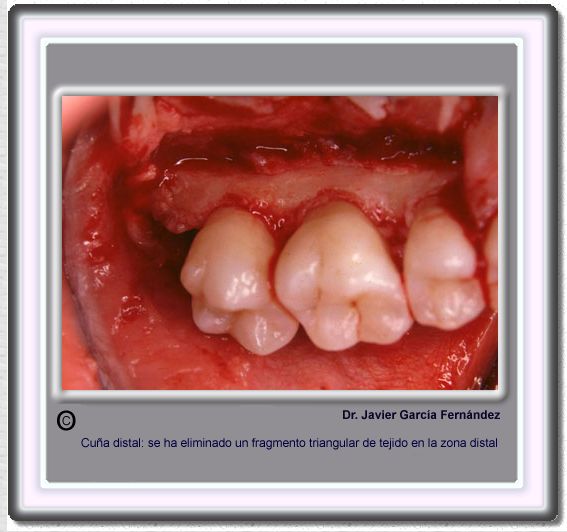

image 169